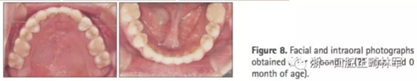

頭側(cè)結(jié)果顯示上頜輕度后縮(SNA 79.1°; A to N,-5.0mm;A到VRP水平距離為57.5mm),下頜輕度前突(SNB,80.2°,Pog-N-7.2mm;POG到VRP水平距離,57.4mm),低角ANB(-1.1°),正常下頜平面角(FMA,29.5°),正常下頜角(119.8°),上頜切牙斜度正常(U2 to SN,106.7°)和下頜切牙的舌傾角(IMPA,85.0°)。正常的覆合和覆蓋(覆合,1.7mm,覆蓋,1.9mm)(圖8和9,表3)。

2年后隨訪提示治療結(jié)果得到保持(圖10,11,表1-3),不同階段的頭側(cè)重疊結(jié)果見圖12。